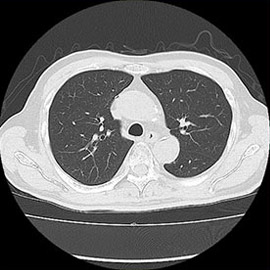

80列マルチスライスCT 検査 画像例

80列マルチスライスCTで撮影した画像

胸部